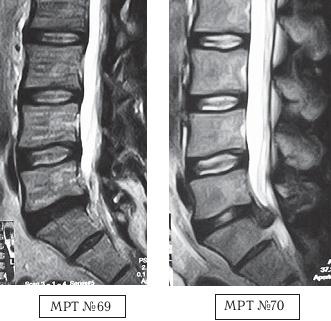

На МРТ № 69 наблюдается сглаженность физиологического лордоза поясничного отдела позвоночника, протрузия в сегменте LV— SI компенсированная спондилёзом, эпидурит на этом же уровне.

На МРТ № 70 того же пациента, наблюдается состояние после четырёх сеансов мануальной терапии, в сегменте LV—SI — секвестрированная грыжа межпозвонкового диска с каудальной миграцией секвестра, абсолютный стеноз спинномозгового канала, сглаженность физиологического лордоза, эпидурит.

Началась данная история с того, что вследствие развития протрузии и эпидурита у пациента появились боли в поясничном отделе позвоночника. По совету знакомых он обратился в центр мануальной терапии. Врач данного центра (мануальный терапевт), осмотрев его и выслушав жалобы, отправил на МРТ-обследование (№ 69). Исходя из результатов обследования, тот же врач назначил пациенту 12 сеансов мануальной терапии. Уже после четвёртого сеанса у больного появилась резкая боль в ноге и онемение. Сделали повторное МРТ (№ 70). Мануальный терапевт ознакомился с его результатом, направил данного пациента в нейрохирургию (но это уже другая история).